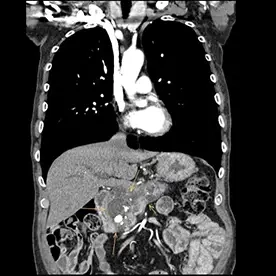

Durchführung einer kontrastmittelgestützten CT-Untersuchung des Abdomens in arterieller und venöser Kontrastmittelphase. Neben einer reizlosen Cholezystholithiasis zeigt sich ein massiv erweiterter D. pancreaticus bis zur Papille und diffuse zystische Pankreasläsionen, teils mit Verkalkungen (Bild 4 und 5) mit dem Hauptbefund im Pankreasschwanz angrenzend an die linke Nebenniere; kein Nachweis solider Anteile (Bild 1). Zusätzlich wurden mehrere kalkdichte Konkremente im Pankreas nachgewiesen, die sich vorwiegend im Bereich des Caput befinden. Keine Lymphadenopathie. Keine metastasensuspekten Herdsetzungen. Als weitere Nebenbefunde wurden eine parenchymverschmälerte Niere rechts und der V.a. auf ein Nebennierenadenom geäußert.

Verdacht auf eine intrapankreatische muzinöse Neoplasie (IPMN) vom Hauptgangtyp. Auch die intra- und extrahepatischen Gallenwege zeigen sich deutlich dilatiert (Bild 2 und 3).